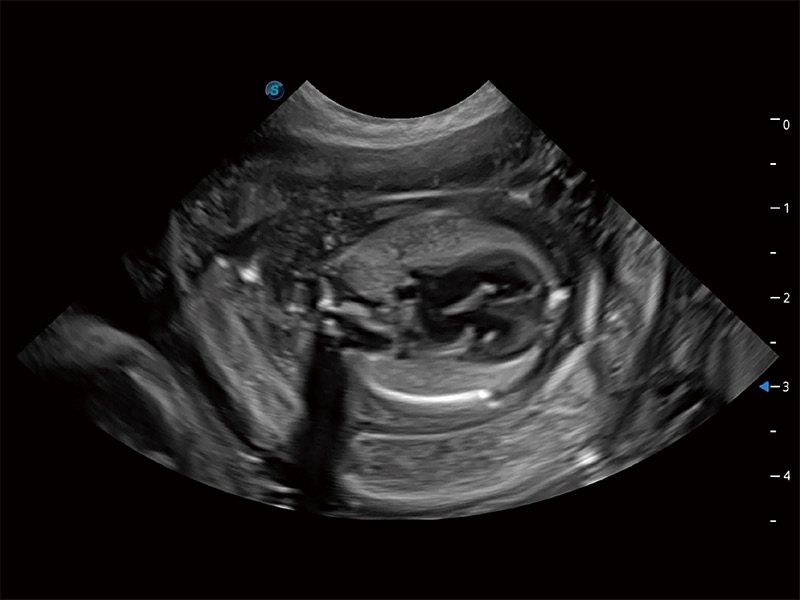

动物是人类最亲密的朋友和最值得信赖的伙伴。银河优越会也一直致力于探索动物专用的超声影像解决方案。全新推出的ProPet系列,是银河优越会在动物超声影像智能化、专业化、精准化的一次跨越式革新。动物不能用言语来表述自己的不适,通过超声影像,ProPet系列搭建了动物医生与不同物种沟通的“桥梁”,为动物医生注入了“治愈之力”。 ProPet 80 是银河优越会匠心打造的一款高端动物专用彩超,采用性能卓越的全新硬件架构,极大提升超声系统的运行效率和数据处理能力,帮助动物医生从容应对日益增多的挑战性病例和日益多样化的临床需求。

ProPet 80 专为动物医生设计,对不同的动物体型和生理结构作出了针对性的优化。通过动物影像专用软件,可满足个性化的应用需求,帮助动物医生获得更精确的诊断数据。

ProPet 80 全新的动物超声智能软件和丰富的探头群,为动物医生提供了高清晰度和精细分辨率的图像,无论在宠物、马科、畜牧还是实验室动物等应用中都可以轻松应对,为您的日常工作带来满意的体验。